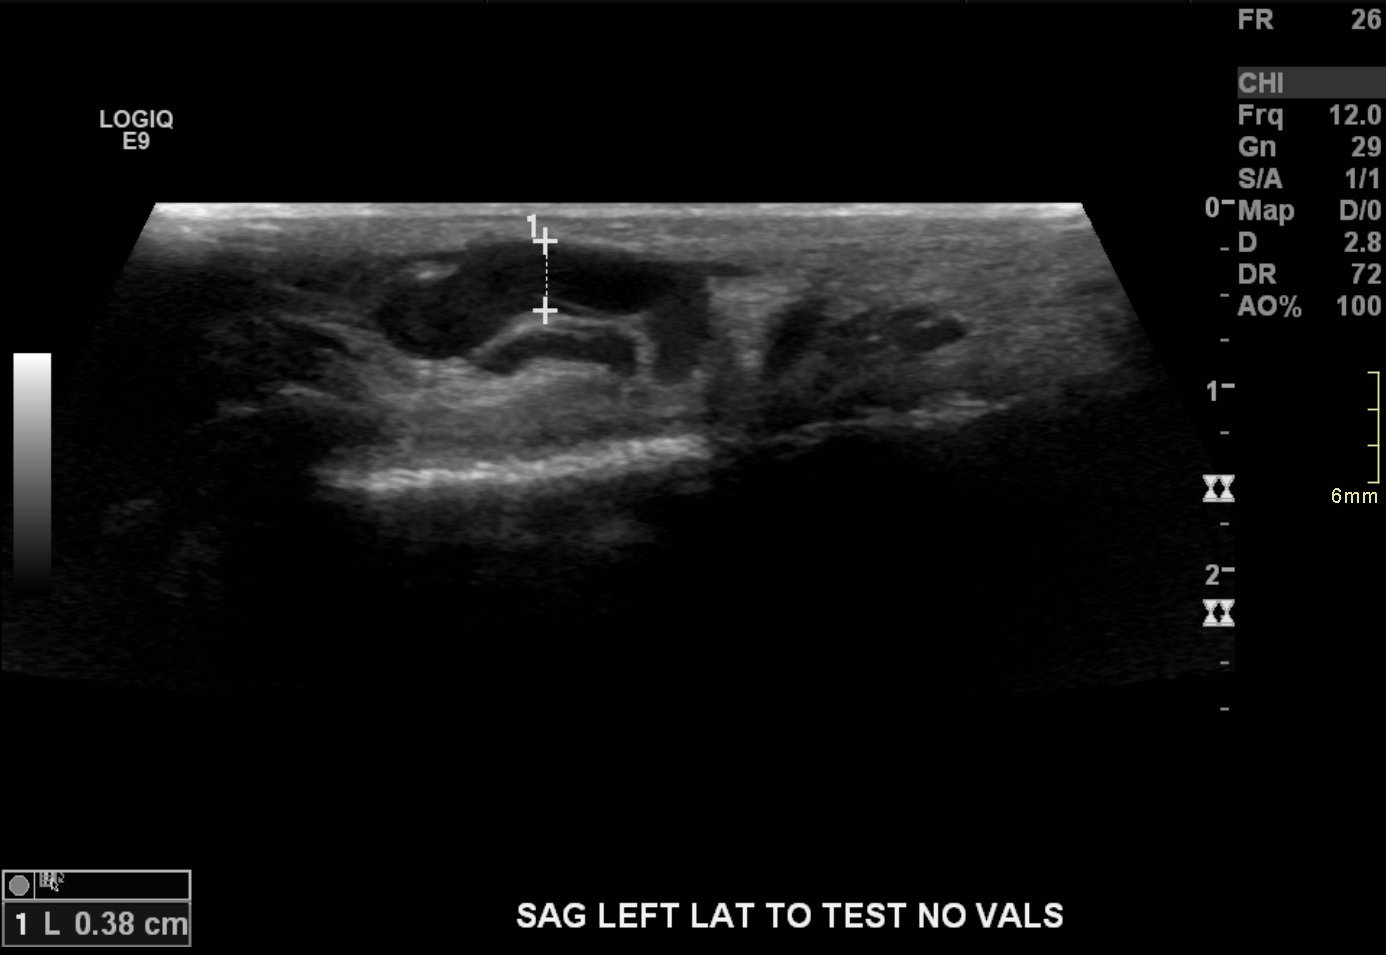

17-year-old male with a long history of left-sided varicoceles status post surgical ligation in 2015 presents with recurrence of symptoms, referred to us for left gonadal vein embolization.

Ultrasound demonstrates enlarged veins (>3 mm) adjacent to the testicle. Angiogram demonstrates reflux of contrast into the left gonadal vein to the level of the scrotum, indicating venous valvular incompetence. Coil embolization and sotradecol sclerotherapy of the left gonadal vein were performed, with an Amplatzer plug at the top of the vein. Repeat angiogram demonstrates no contrast opacification of the vein. Red arrows indicate the left gonadal vein and the blue arrows indicate the left renal vein.